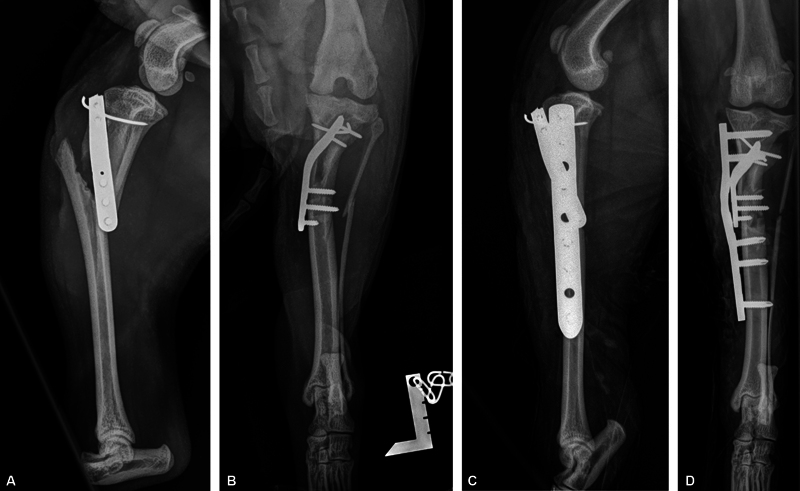

Objectives:  To evaluate the outcome and complications in dogs with medial patellar luxation (MPL) undergoing tibial tuberosity transposition (TTT) with a locking plate and pin fixation (Plate-Pin).

Methods:  This retrospective multicenter study included 65 consecutive MPL stifle surgeries using tibial tuberosity (TT) fixation with a 5-hole locking plate and a pin. The median weight of the dogs was 6.2 kg. The grade of luxation was 2/4 in 50 stifles and 3/4 in 15 stifles. Outcomes were assessed during follow-up examinations 33 to 648 days after surgery with clinical examination and radiography. Canine Orthopedic Index questionnaires were sent to owners 6 to 39 months after surgery.

Results:  Complications were reported in 14/65 stifles, of which 8/14 were minor and 6/14 were major. After treatment of the major complications, lameness was resolved in all cases and the MPL was resolved in 64/65 stifles.

Clinical significance:  When the surgery was performed as described in this article, Plate-Pin fixation for TT during MPL surgery is a feasible technique with a lower incidence of luxation recurrence, TT avulsion, and fractures compared with recent retrospective studies with pin and tension band wire TT fixation. Further development of the locking plate TT fixation is indicated to resolve pin-related complications and to determine if fixation including a pin is necessary.